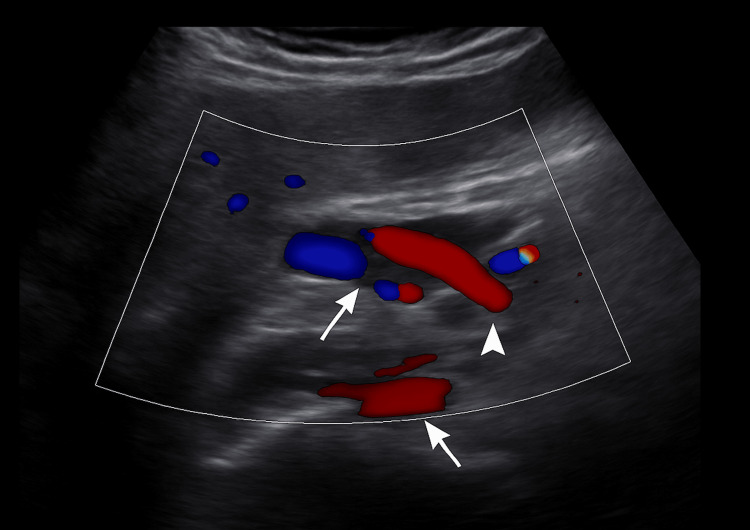

Ultrasound showed intra- and extrahepatic bile duct dilatation (CBD: 15.8 mm), the absence of gallbladder consistent with prior cholecystectomy, and a starry sky pattern. Doppler ultrasound demonstrated the intrapancreatic portion of the CBD and its vascular relations (Figure 1), followed by a confirmatory image with biliary catheter in situ (Figure 2).